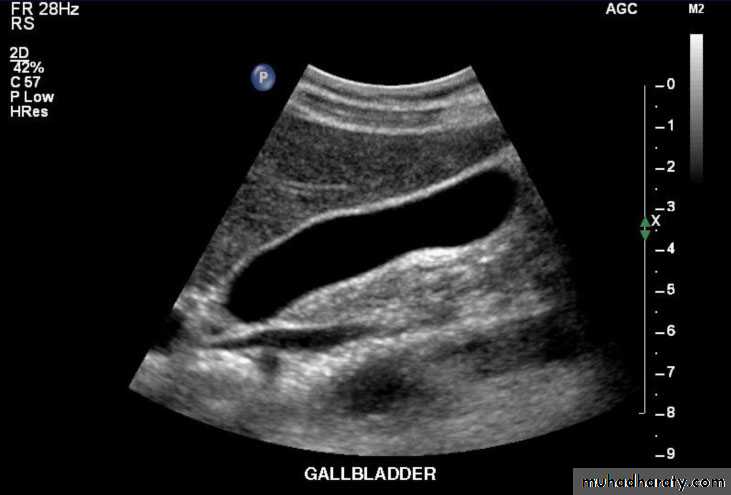

Gall bladder ,biliary tree

Fasting

CBD not > 7mmnormal intrahepatic tree is too small to seen

• no contrast.Gall stone & cholecystitis